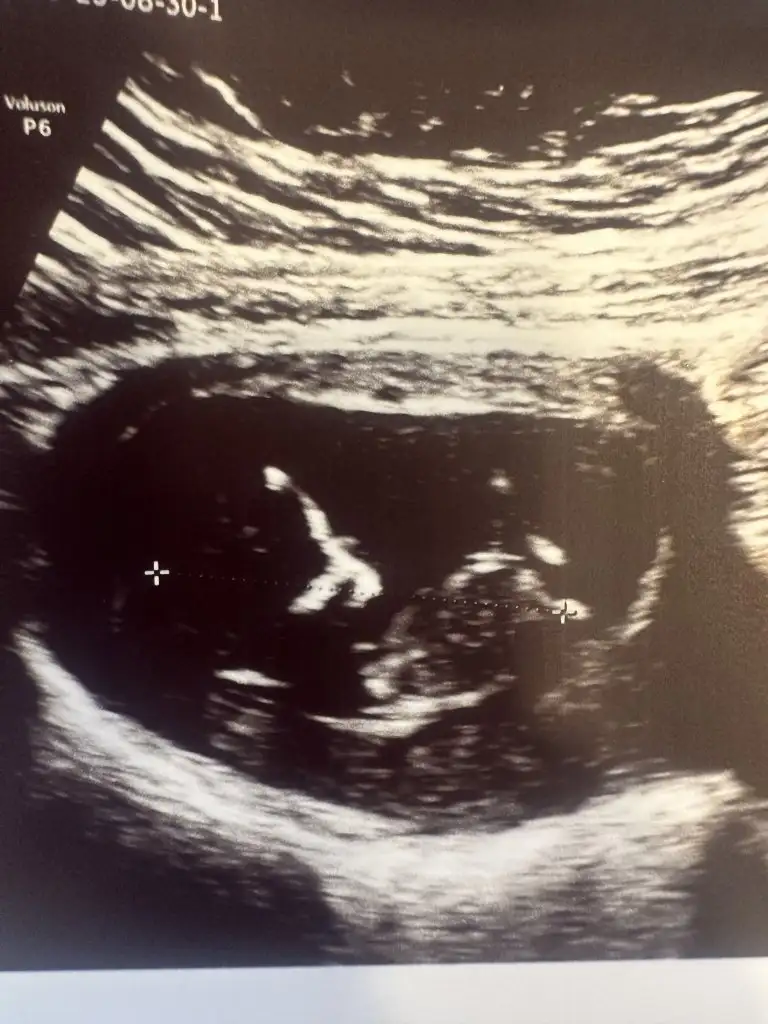

Arkadaslar benimde bebegimin cinsiyetinde bir tahmininiz var mi? Ramzi teorisine göre bakabilen varsa memnun olurum

11+5 haftalik karindan